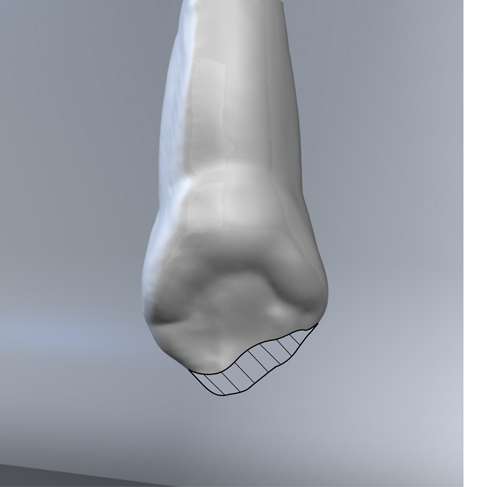

En ciertas áreas del saber humano, el lenguaje confuso o criptográfico Muchas son las técnicas elaboradas para lograr un desgaste selectivo, y numerosos autores han expuesto en su momento variadas formas de lograr una función oclusal fisiológica mediante el ajuste de la misma. Han pasado años desde entonces y, sin embargo, aún hoy, un altísimo porcentaje de profesionales “navega” por el mar de la confusión oclusal, dada la diversidad de conceptos y escuelas, sin lograr arribar a costa alguna donde poder anclar un conocimiento sólido sobre cómo tratar la oclusión Ya se esté realizando una simple obturación, endodoncia, incrustación, radectomía u ortodoncia, la lógica pocas veces, en la mayoría de los casos, vincula un tratamiento con otro, siendo el resultado final el mismo caos inicial; enmascarado por mucho tratamiento profesional. El ajuste oclusal es un medio inicial de proveer al sistema enfermo de: Dicha técnica, que puede ser terapéutica en sí misma; consta de dos etapas, a saber: 1) Ajuste Oclusal por Adición Mediante el estudio de la guía anterior, encargada de efectuar las Disclusiones durante las excursiones mandibulares, podremos observar si ésta es funcional o no. • Marcas de carácter continuo, si en ese recorrido se produce la Disclusión de los sectores posteriores y todo marcha correctamente. FIG 1-2 Si por el contrario observamos: • Marcas de carácter discontinuo, significa que dicha Disclusión se está efectuando por medio de una pieza dentaria posterior a la guía anterior. FIG 3-4-5 (FIGS. 3, 4 Y 5). En la figura 6 las flechas indican, en un caso clínico de análisis oclusal, la presencia de marcas discontinuas que indican Interferencias en Propulsiva. FIG 6-7 Y por último, si existieran: • Abrasiones de las áreas discluyentes en las áreas de diagnóstico de la guía anterior, deberemos aportar material a dicha zona para no permitir el choque lateral de las piezas posteriores (Ajuste Oclusal por Adición) En las imágenes 11 y 12 podemos observar la adición de composite en la punta de un canino derecho, previa la observación de la Faceta Parafuncional remarcada durante el análisis oclusal en el articulador. (FIGS. 8 A 12). 2) Ajuste oclusal por Sustracción o Desgaste Habiendo cumplido ya con la verificación de la funcionalidad de la Guía Anterior, comenzamos los desgastes en céntrica, a fin de lograr un único arco de cierre, guiado eficazmente por la Guía Anterior; es decir: la coincidencia entre Oclusión Habitual y Oclusión en Relación Céntrica. En este caso, intentar gastar dichos puntos, de ser posible sólo en las cúspides de corte o no fundamentales: • Crestas Triangulares Internas, Cúspides Vestíbulares Superiores • y un poco de las Crestas Triangulares Internas, Cúspides (FIGS. 13 A 16). Si la deflección es hacia el lado opuesto, se invierten los desgastes. En las migraciones hacia adelante, las únicas razones posibles están en los puntos estabilizadores (FIG. 17); es decir: -Vertientes Distales de los Rebordes Marginales, Triangulares (FIG 17) (FIG 18 A-B-C-D) Obsérvese cómo, en una boca prácticamente entera, comienzan a “desmoronarse” prismas adamantinos (FIG. 19), como consecuencia de un punto prematuro de contacto, ubicado en la posición de un estabilizador, que provoca la discrepancia horizontal postero-anterior causante de dicho efecto (FIG. 20). FIG 19-20 Dicho punto, será necesario ajustarlo antes de cualquier tratamiento en la zona ¿Cuáles serían las consecuencias si esos incisivos fueran implantados tal como es frecuente observar en múltiples congresos y cursos de implantología, donde el tema de la oclusión no es más que un cuadro polifacético y anecdótico? 14 15 16 17 Todo producto del adelantamiento mandibular Realizados ya los desgastes en céntrica, obteniendo de esta manera un único arco de cierre, es decir, oclusión en relación céntrica, debemos realizar el ajuste de las excéntricas, apoyando la acción de la guía anterior, para lo FIG 22 a. De un lado a otro de un mismo maxilar, la imagen es especular, o sea invertida. b. En hemimaxilares cruzados, la imagen es idéntica. Allí donde existan colisiones entre cúspides, se deberá crear un surco para que dicha cúspide antagonista migre a su través, tanto en el lado de no trabajo, como en el de trabajo y en el de propulsión. FIG 23 Es importante conservar esta parte del surco, ya que si no existieran, los contactos entre cúspides serían en superficie y no puntiformes (fig. 24). FIG 24 1. Obtener un único arco de cierre con coincidencia entre oclusión habitual y relación céntrica. 2. El cierre mandibular debe ser recibido sólo por la tabla premolar-molar. 3. Durante las excursiones funcionales es la guía anterior la que debe sufrir las fuerzas laterales. 4. De cumplirse estas dos premisas debemos obtener libertad de desplazamiento (no confundir con libertad en céntrica) a las piezas posteriores mediante la creación de surcos disclusivos. Examinadas ya las posibles migraciones mandibulares y los desgastes o aposiciones necesarios para poder ocluir en céntrica, es fundamental recordar que, previamente a todo tipo de ajuste, se ha hecho necesario ubicar a la mandíbula en relación céntrica. Para ello debemos utilizar el propio funcionalismo muscular 22 FIG 25 Y esto no significa otra cosa que: piezas dentarias estables en todos los planos del espacio, ATM centrada en la cavidad glenoidea, periodontos sin tensión, músculos en la dimensión de elongación adecuada para un fisiologismo Paz absoluta en la intimidad del Sistema Estomatognático. Y así, como corolario final, es posible establecer una regla de oro similar en importancia a la conocida formula: Forma = Función Ésta es: FIG 26 FUNDAMENTOS NEUROFISIOLÓGICOS DEL REGISTRO DE OCLUSIÓN EN RELACIÓN CÉNTRICA ( ORC) MEDIANTE EL USO DE LAMINILLAS DE LONG CUADRO